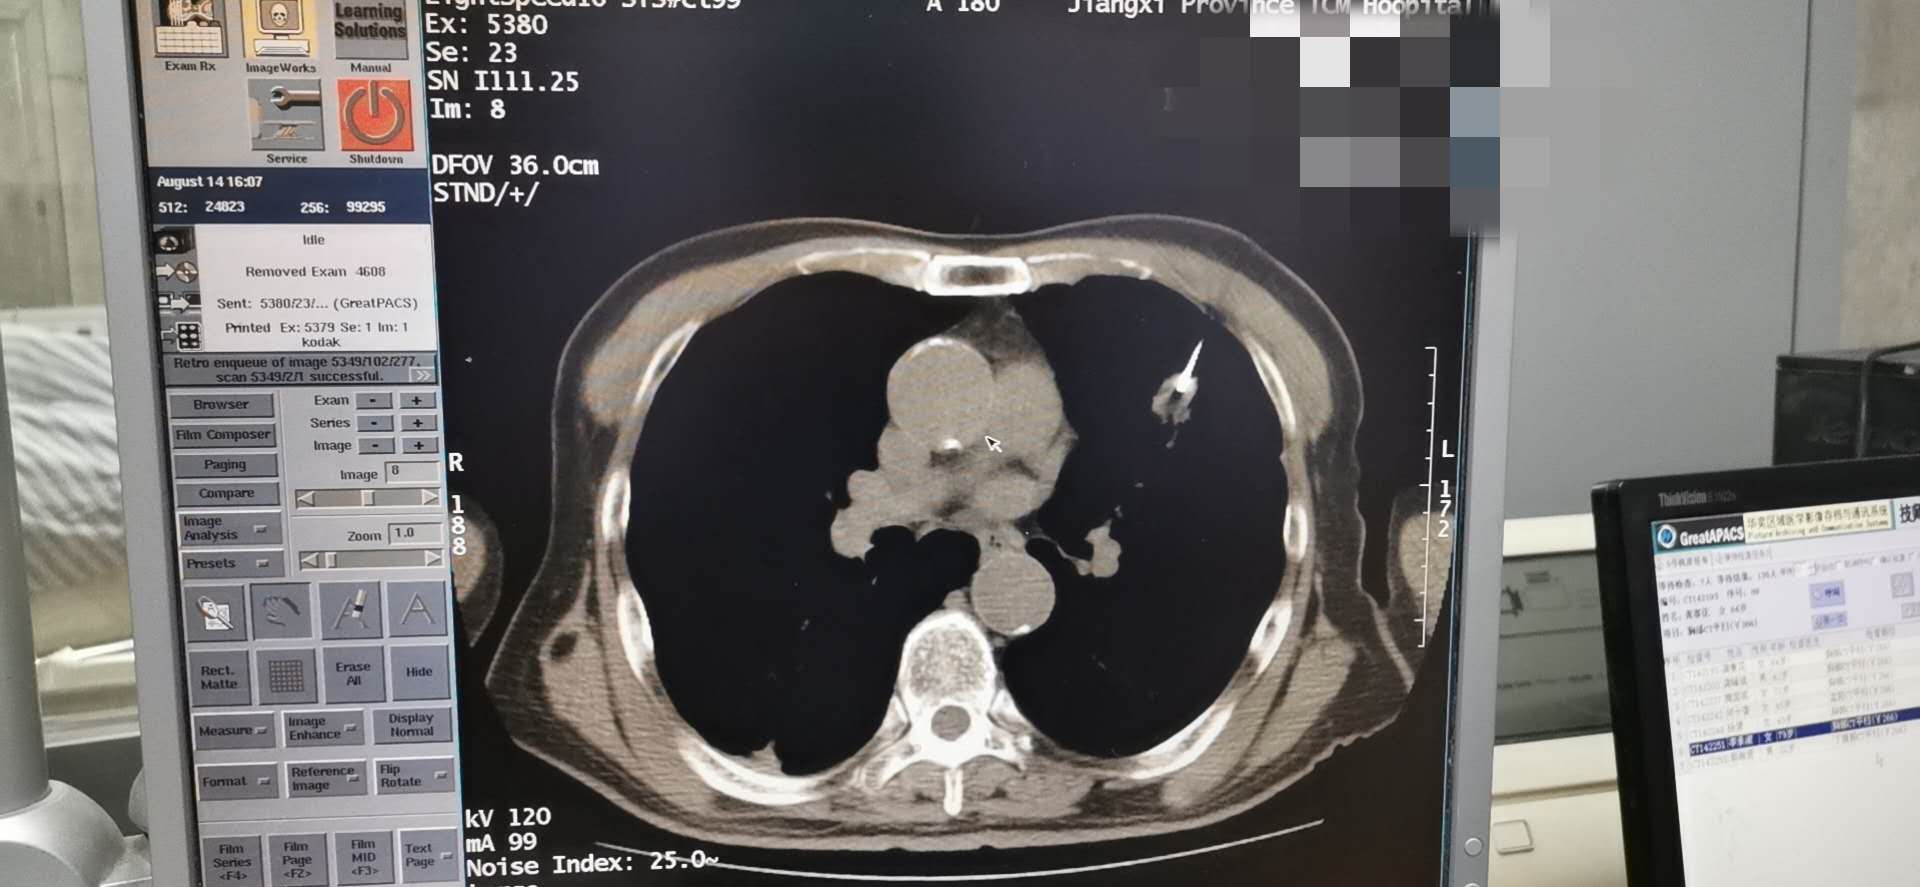

我院肿瘤科8.14于CT引导下完成肺穿刺术